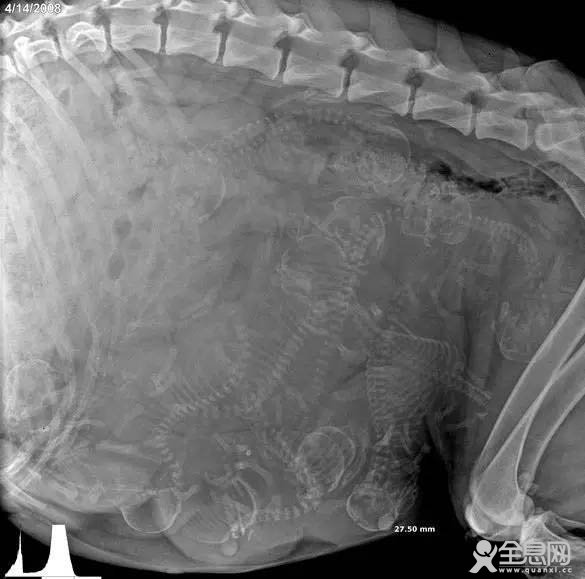

这是怀孕的狗狗,满肚子挤挤仄仄的小生命。